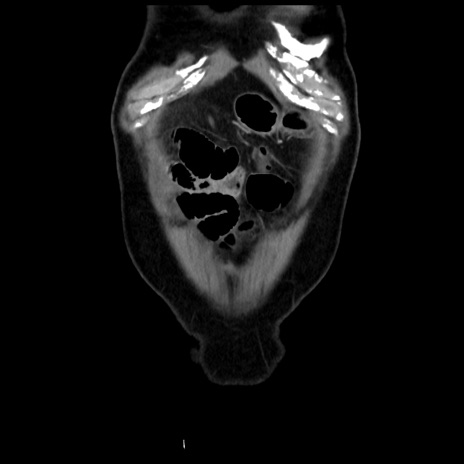

症例16(冠状断像)

【現病歴】 約1ヶ月前より間欠的に腹痛と嘔吐あり、当院消化器内科を受診したところCTで多発する肝臓のLDAを指摘され、精査中であった。以降は消化器症状は安定していたが、2日前より嘔気と腹痛があり、同日より排便・排ガスが消失した。改善認めず、 本日、救急外来を受診した。